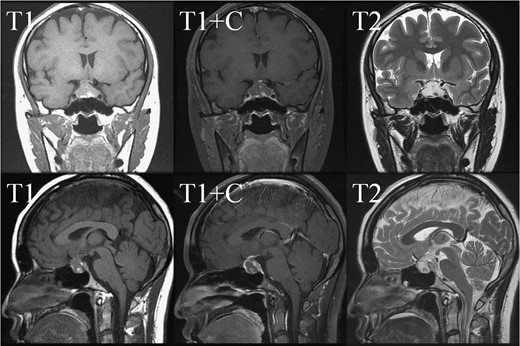

In May 2018, a 28-year-old woman with medical history of sick sinus syndrome and mitral valve prolapse, who just gave birth to a child in April 2018 coming to our Emergency Department with the chief complaint of severe headache and blurred vision for one week. At the Emergency Department, her visual acuity was 0.1 on her right eye and 0.9 on her left eye. Brain CT (computed tomography) scan was checked showing increased soft tissue density over sellar and suprasellar regions, more on the right side. Sellar MRI (magnetic resonance imaging) (Fig. 1) was further arranged which showed a mass with rim enhancement about 2.2 cm ×1.4 cm ×1.2 cm in size located at sella with suprasellar extension with several suspected hemorrhagic foci inside. Under the impression of pituitary apoplexy, she was admitted for further evaluation and management. On admission, her neurological examination showed essentially negative findings except declined right visual acuity; her hormone study showed low level of cortisol (cortisol<1.00 μg/dL) and others were within normal limits. Before surgery, ophthalmologist was consulted again to repeat her ophthalmological examination. The visual acuity of her right eye and left eye improved to 0.8 and 1.0 respectively after the use of steroid. The visual field test showed peripheral defect over the upper visual field of both eyes. Under general anesthesia, she underwent endoscopic endonasal transsphenoidal approach with the removal of tumor and skull base reconstruction. Grossly, the tumor was yellow and soft in consistency and at the end of the procedure, the pituitary gland was well exposed and visible (Fig. 2). After surgery, her vision was subjectively improved; her cortisol level returned to normal (cortisol=16.6ug/dL) and other hormonal data were within normal limits. Histology examination of the tumor (Fig. 3) showed that it composed of spindle to epithelioid cells forming poorly defined lobules and interlacing fascicles, both featuring eosinophilic and oncocytic cytoplasm, with mild nuclear atypia. Immunohistochemically, the neoplastic cells showed TTF-1(+), GFAP(-), EMA(+) Annexin A1(+), and PAS/DPAS(-). Based on the result of histopathology findings and immunohistochemical stains, spindle cell oncocytoma was diagnosed. Before discharge home, her early post-operative sellar MRI (Fig. 4) showed neither residual nor recurrent lesion; she was discharged in a good condition.

Pre-operative sellar MRI. The coronal view (upper row) and sagittal view (lower row) demonstrated a mass about 2.2 cm ×1.4 cm ×1.2 cm in size, located at sella with suprasellar extension. The mass lesion showed low intensity in T1 weighted image, high intensity in T2 weighted image, and rim enhancement after gadolinium injection. Inside the mass, several foci showing high intensity in T1 weighted image, low intensity in T2 weighted image and no enhancement after gadolinium injection were present.